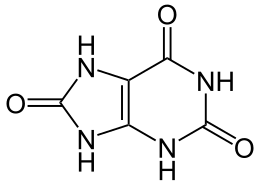

Although findings have varied, usage of nonsteroidal anti-inflammatory drugs (NSAIDs) like ibuprofen may be neuroprotective.[129][130] Calcium channel blockers may also have a protective effect, with a 22% risk reduction reported.[131] Higher blood concentrations of urate—a potent antioxidant—have been proposed to be neuroprotective.[125][132] Although longitudinal studies observe a slight decrease in PD risk among those who consume alcohol—possibly due to alcohol's urate-increasing effect—alcohol abuse may increase risk.[133][134]